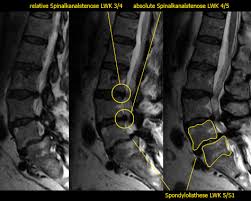

Spinalkanalstenose Sks Symptome Und Diagnose

Degenerative Erkrankungen Der Wirbelsaule Springerlink